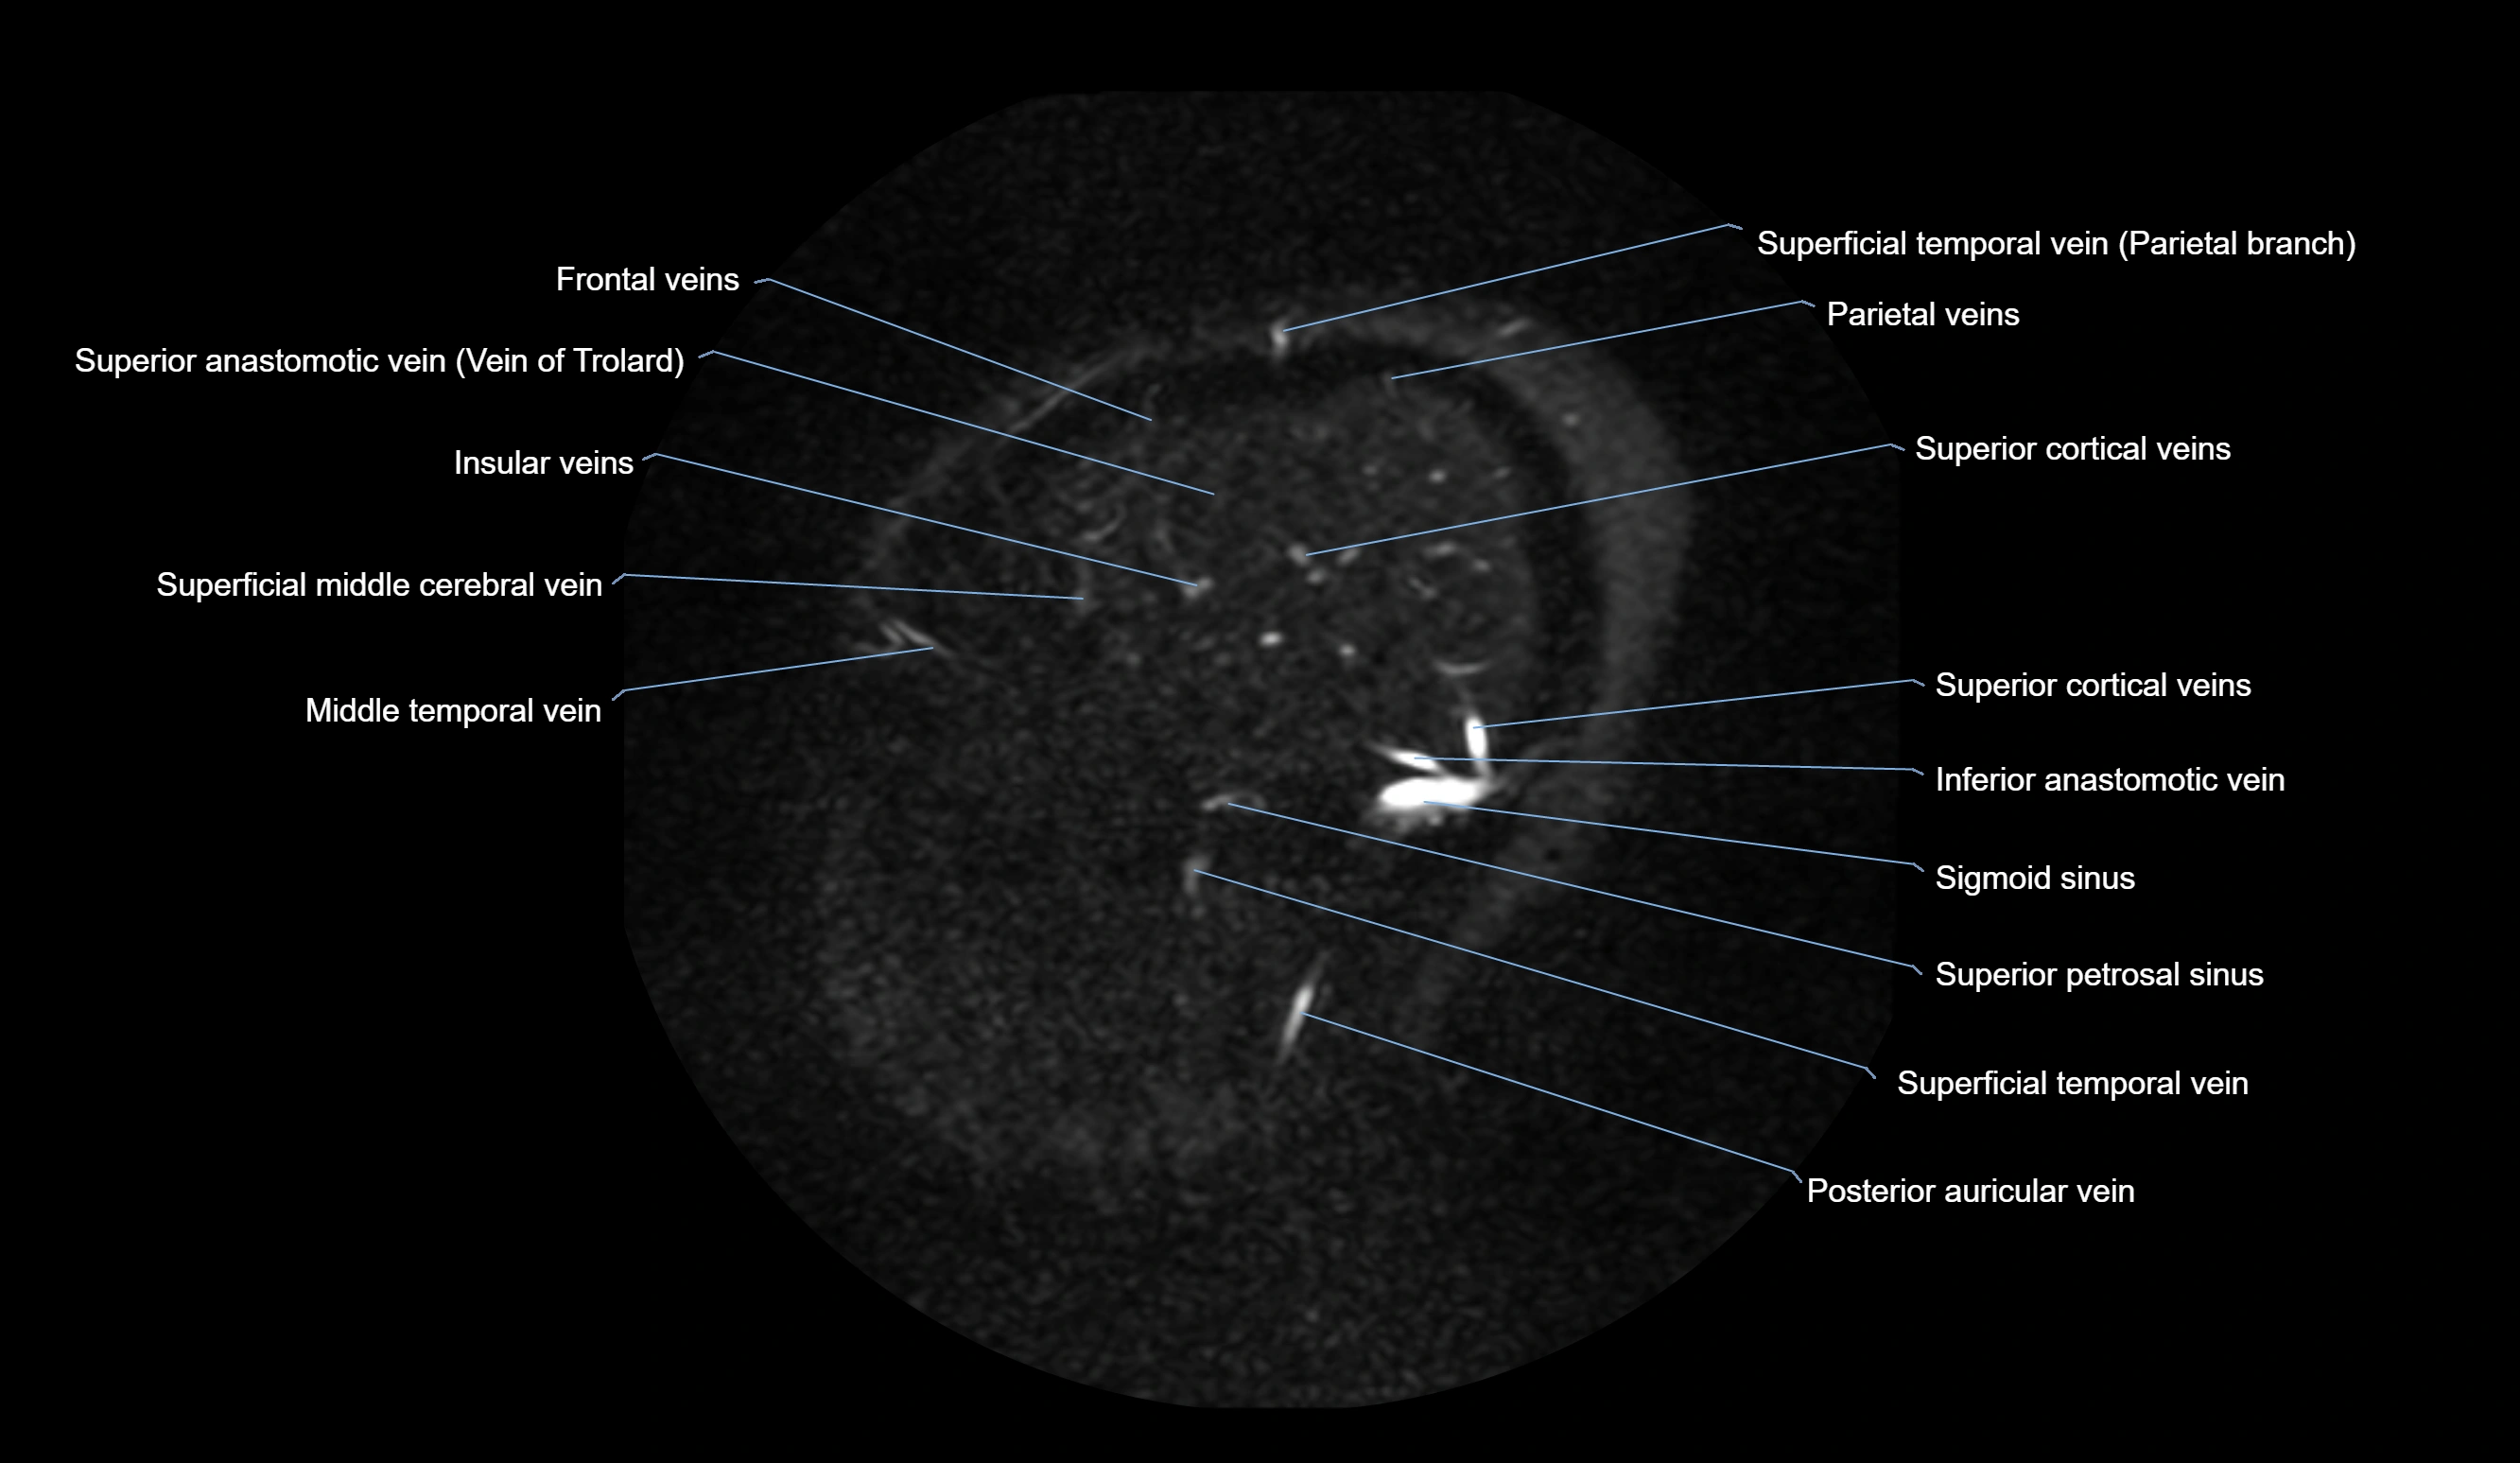

MR Venography (MRV):

• Time-of-flight (TOF) or contrast-enhanced MRV shows the angular vein as a bright enhancing venous channel

• Clearly demonstrates its continuity with the facial vein and superior ophthalmic vein

• MRV is highly useful in evaluating thrombosis, venous obstruction, or collateral venous drainage

MRI images